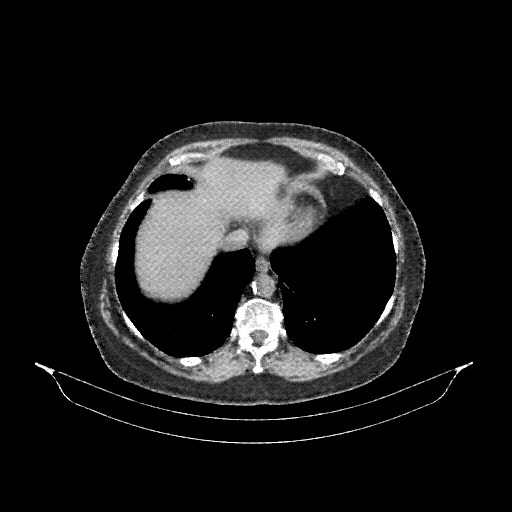

Generated VENOUS CT scan (A→B translation)

Full window (WL 1023.5, WW 4095 β†’ Low βˆ’1024, High +3071)